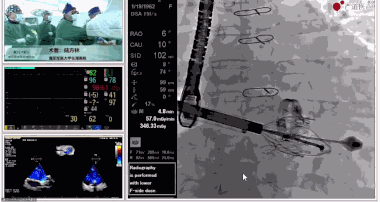

圖片

▲瓣膜植入后釋放的過程

在手術(shù)直播中瓣膜植入過程不到10分鐘,手術(shù)獲得圓滿成功,充分體現(xiàn)徐志云、陸方林團(tuán)隊(duì)技術(shù)精湛,團(tuán)隊(duì)協(xié)作默契及器械的優(yōu)越性。

該例患者返回后當(dāng)天拔除氣管插管,生命體征穩(wěn)定,恢復(fù)良好。此次會(huì)議不僅有最前沿的學(xué)術(shù)講座,更有3D體驗(yàn)般的手術(shù)直播,為大家第一視角直觀呈現(xiàn)領(lǐng)域新技術(shù)、新策略、新思路。